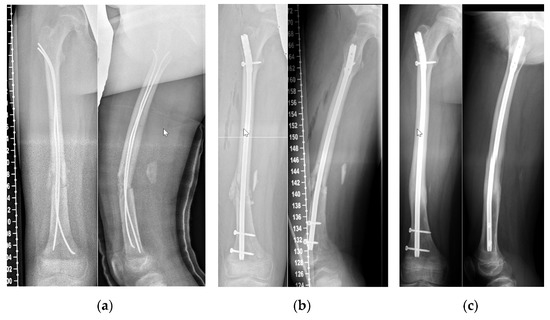

4.2. Demographics, Radiographic Analysis and Complications